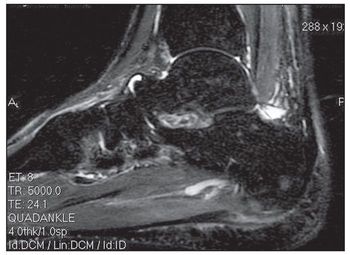

A 31-year-old Asian man presented for evaluation of left foot pain that began on the day before his clinic visit while he was practicing parkour (the physical discipline of training to overcome obstacles within one’s path by using only the human body and objects in the environment). He had no significant medical history. The patient recalled leaping from a platform toward a horizontal bar attached to a wall a few feet away. During the lift-off phase of the jump, he experienced a snapping sensation in his left foot, with subsequent pain in the arch and heel. Immediately after this event, he was unable to ambulate.